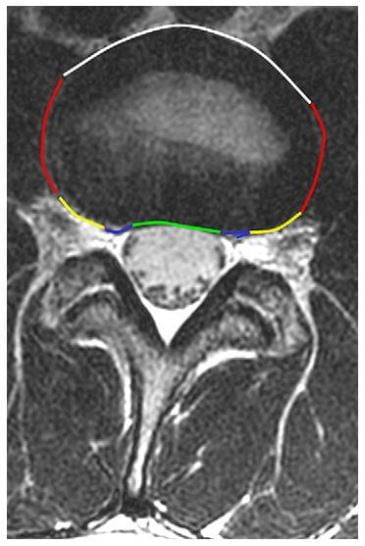

Hình 11. Hình axial T2w ngang qua đĩa đệm L3-4 chỉ ra các vùng đĩa đệm khác nhau được xác định trên hình axial. Đoạn đường màu xanh lá cây chỉ ra vùng trung tâm, đường máu xanh biển chỉ ra vùng dưới mặt khớp, đường màu vàng chỉ ra vùng lỗ liên hợp, đường màu đỏ chỉ ra vùng ngoài lỗ liên hợp và đường màu trắng là vùng phía trước.